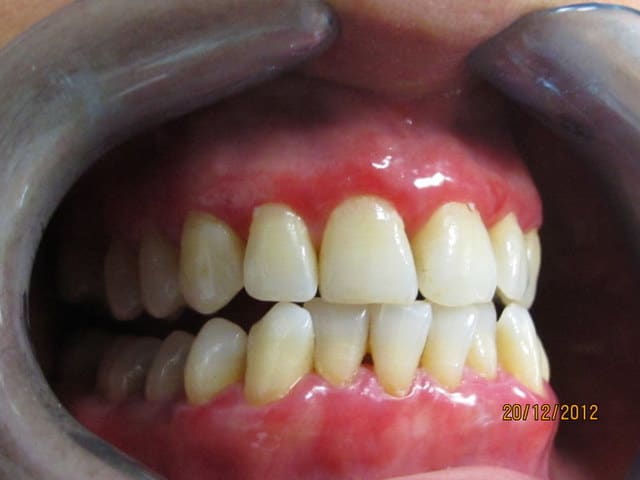

Je viens de voir cette patiente, qui consulte pour le problème esthétique lié à la couleur très gênante de sa gencive.

Cette patiente, originaire d’Afrique du nord a la trentaine, pas de pathologie générale connue, pas d'allergie.

elle a été traitée il y a 2 mois par surfaçage et motivation aux soins locaux qu'elle applique plutôt sérieusement.

Au sondage pas de poche, quasiment pas de saignement.

La couleur rouge s'estompe à la pression, on sent la gencive très fine et lisse.

Aucune douleurs.

Ca me rappel le cas d'une patiente qui avait une penphigoîde, qu'en pensez vous ? On voit sur les photos des trace qui pourrait laisser penser à des desquamations de bulles.

Tes photos ressemblent bien à un cas de stomatite pemphygoïde que je viens d'avoir.

Un truc simple pour avancer dans ton diagnostic --> frotte très doucement le manche du miroir sur la gencive là ou elle est le plus rouge, si une bulle se forme spontanément cela confirmera le diagnostic.

Si ce n'est pas le cas et que les lésions érosives durent dans le temps malgré une meilleure hygiène, adresse-la à un bon dermato qui fera le dépistage nécessaire pour exclure une maladie auto-immune.

tu as bien fait l'examen de ta patiente: elle n'a pas probablement pas de problème parodontal profond. Elle présente un lichen étendu à l'ensemble de la gencive. C'est un de ces cas que présentait le professeur Monique Brion pour mettre en garde contre les traitements parodontaux abusifs. Présente souvent des poussées inflammatoires douloureuses.

Evidemment il peut aussi se combiner à des problèmes de gingivites et de parodontites.